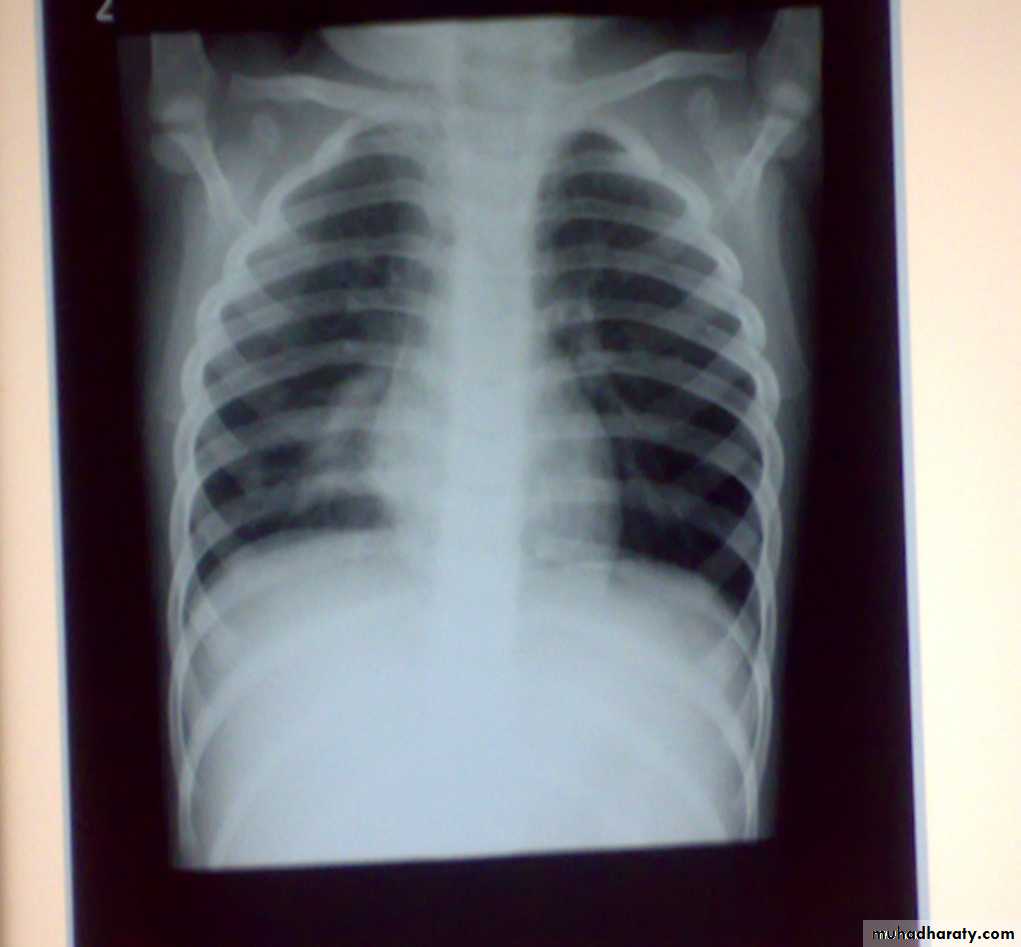

• Normal Bronchoscopic Findings

• Abnormal Bronchoscopic Findings